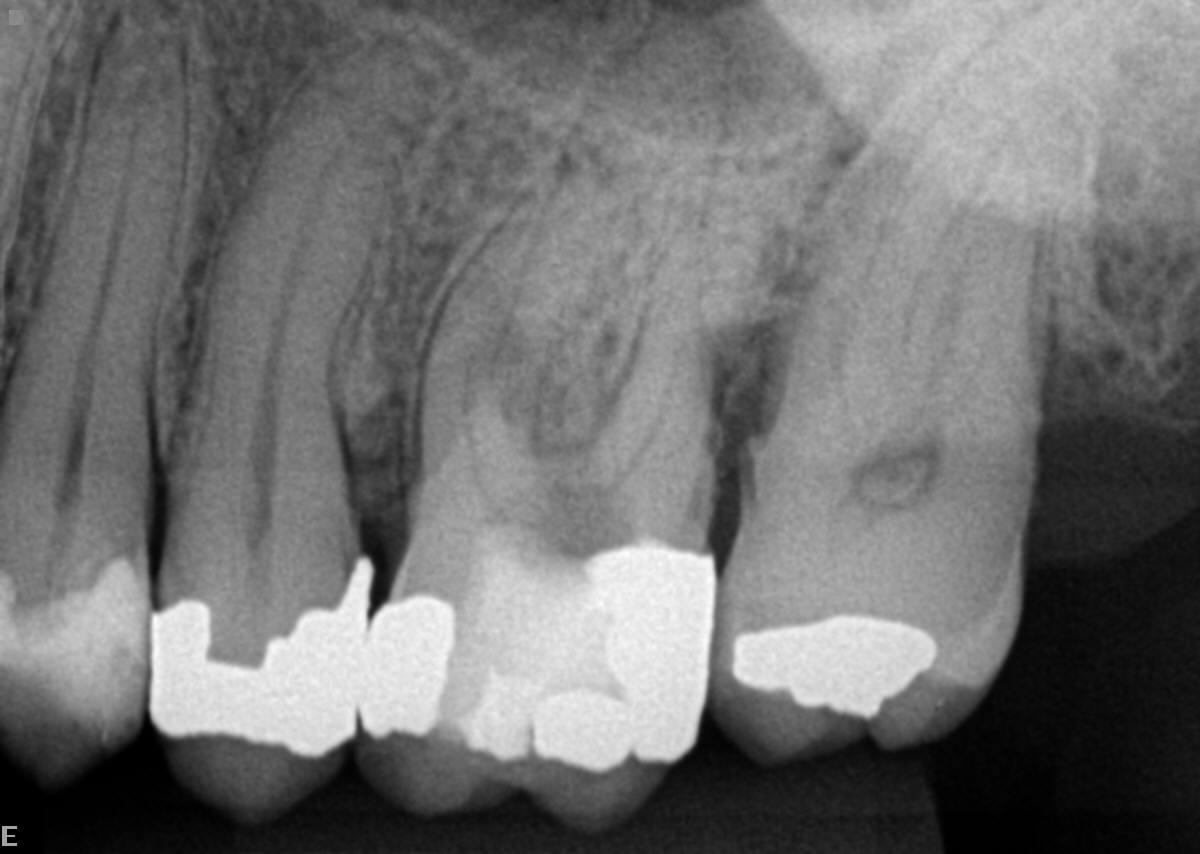

Paciente compareceu ao consultório encaminhado por um colega que executou a abertura do dente. Porém, na dificuldade de localização da câmara pulpar, acabou perfurando acidentalmente o assoalho do dente (Figura 1 e Figura 2).

Realizamos a abertura do dente com a broca diamantada esférica de haste longa em alta rotação número 1016. Logo após a abertura, já foi possível localizar a perfuração em assoalho pulpar (figura 3).